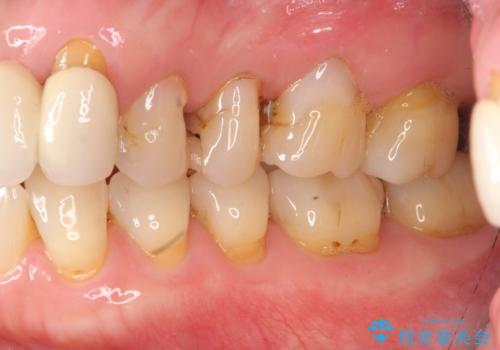

歯ぎしりに抵抗する歯周補綴 インプラント補綴

- 朝起きると歯が痛く歯ぎしり、歯の揺れの改善を求めて来院されました。

噛み合わせ・歯ぎしりにより、歯周病を発症し感染のコントロール、強い咬合力のコントロールをできるような補綴計画をたてます。

分岐部病変を併発していた歯は、抜歯としインプラントによる咬合機能の回復。残すことのできる歯は歯周治療後連結補綴を行い歯ぎしりに対抗します。